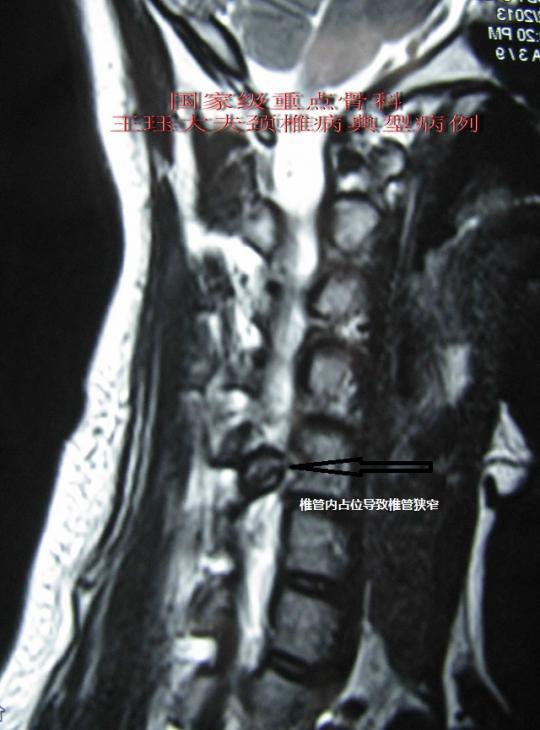

病例4:颈椎管内占位性病变压迫神经

540x730 - 44KB - JPEG